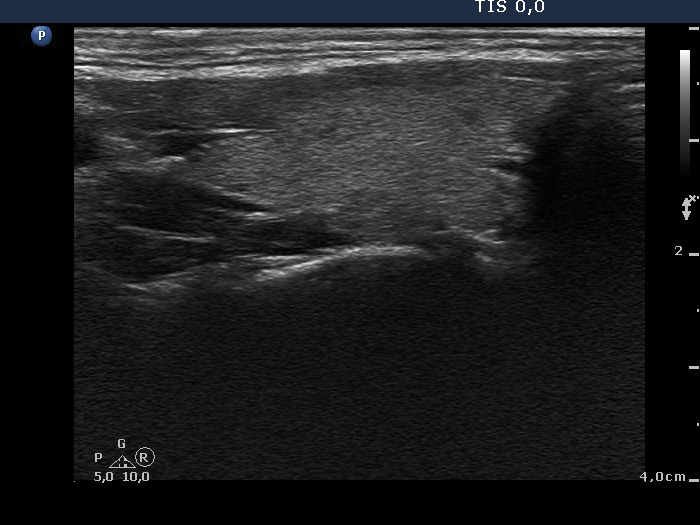

Right lobe, transverse scan